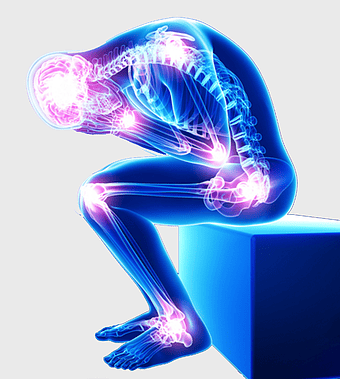

Joint Hydrolyzed collagen Gel, human musculoskeletal system, joint pain relief, electric blue anatomy, skeletal health benefits, muscle support supplement, arthritis treatment options -

rheumatoid arthritis illustration, chronic pain therapy, joint replacement surgery, blue violet human skeleton, skeletal anatomy diagram, arthritis pain relief methods, orthopedic health visual aids -

arthritis pain symptoms, rheumatoid arthritis illustration, joint pain areas, human body anatomy, skeletal health issues, medical visualization, chronic joint discomfort -